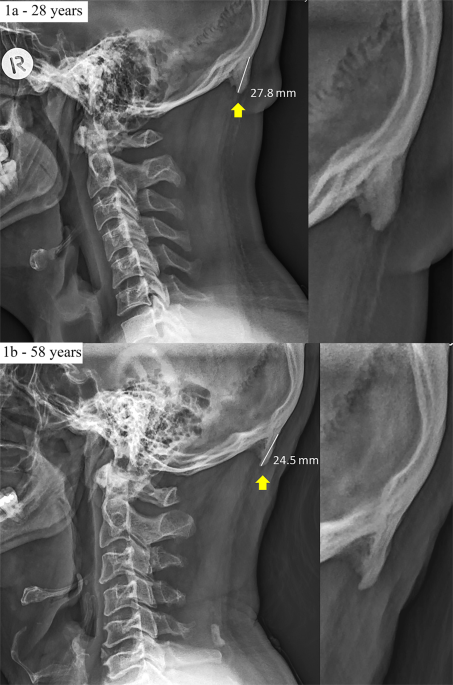

Researchers from Australia say cell phones might be the reason young adults are developing “enlarged external occipital protuberance” (EEOP). The occipital bone is the main bone of the lower part of the skull. What the scientists are saying is that our bodies are adjusting to worsening posture by growing a horn-like spike at the base of our skulls to relieve pressure induced by hours spent hunched over our phones.